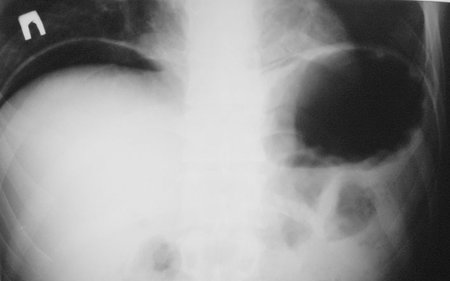

- Фрагмент обзорной рентгенограммы БП

На узи газ под печенью,на обзорной рентгенограмме газ под правым куполом диафрагмы т.е. мы имеем

типичную перфорацию полого органа.

Да,все верно, перфорация язвы желудка, свободный газ в брюшной полости.